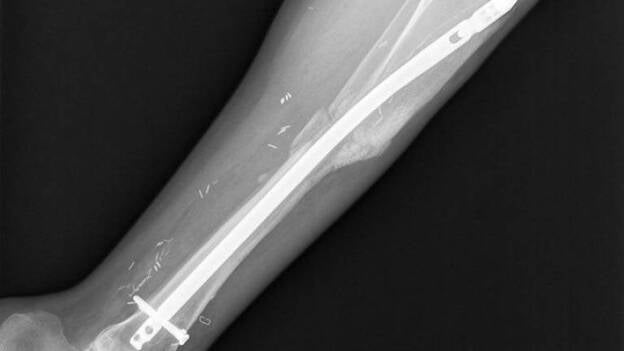

Medicina Regenerativa/PRP y Células Madre